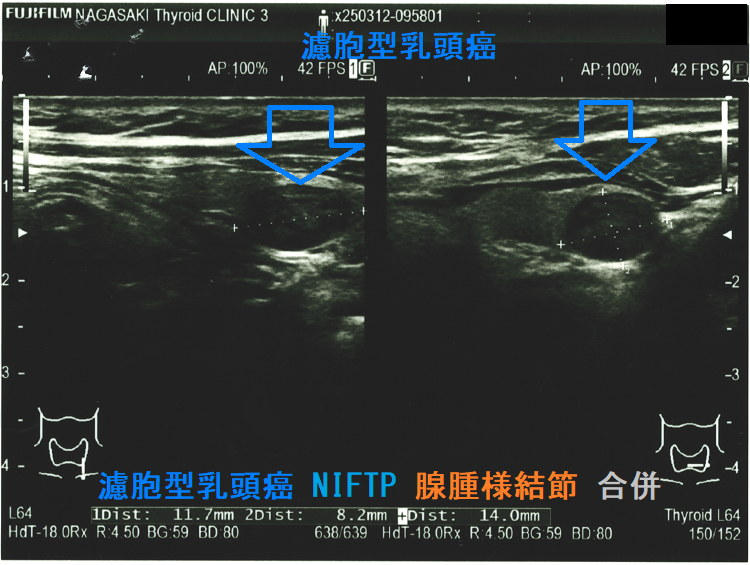

Non-invasive follicular thyroid neoplasm with papillary-like nuclear features (NIFTP) 超音波(エコー)画像;見かけは濾胞型甲状腺乳頭癌、濾胞性腫瘍と鑑別できまない

(a)Non-invasive follicular thyroid neoplasm with papillary-like nuclear features (NIFTP) 超音波(エコー)画像;見かけは濾胞型甲状腺乳頭癌、甲状腺濾胞癌、腺腫様結節と鑑別できまない

Non-invasive follicular thyroid neoplasm with papillary-like nuclear features (NIFTP)の超音波(エコー)所見は、

- 被膜が存在(被膜のない場合もある)

- 充実性、等エコーが多い

- 砂粒状石灰化を認めない

などで、濾胞型甲状腺乳頭癌、濾胞性腫瘍(良性濾胞腺腫 、甲状腺濾胞癌)と鑑別できません。砂粒状石灰化のない濾胞型甲状腺乳頭癌なんて普通に存在します。NIFTPの60.1%は悪性を疑う所見が無いとされます[Endocrine. 2021 Jul;73(1):131-140.]。